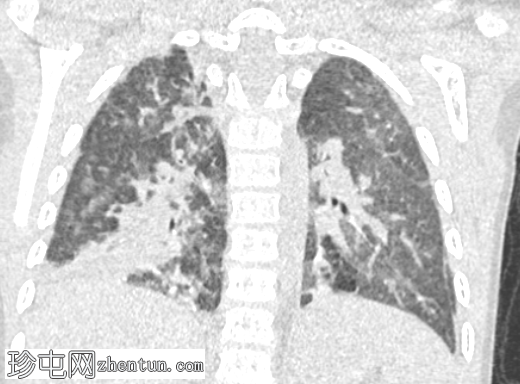

CT

3.png

冠状位增强扫描

动脉期

冠状位

肺窗

横结肠及其系膜经膈前部缺损疝入前纵隔。

未见肠管扩张或梗阻。

双肺实变影,提示呼吸道感染。